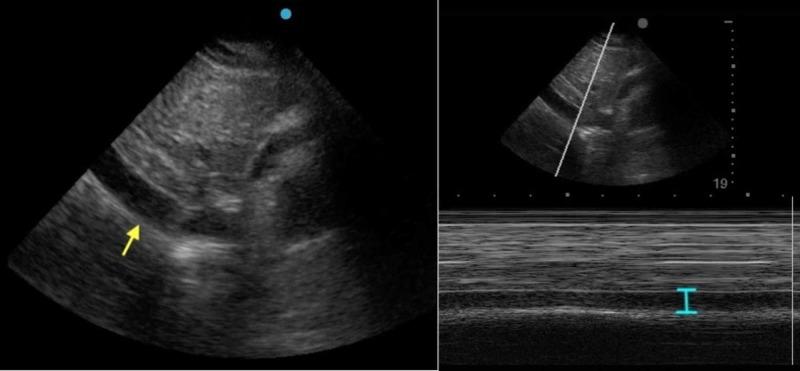

Influenza A and B acute infections usually affect primarily the respiratory system. In rare cases, however, the cardiovascular system is also compromised either via the direct effect of the virus or via the worsening of preexisting cardiac conditions. We present a rare case of acute Influenza B infection presenting as pericardial effusion and cardiac tamponade. A healthy 32-year-old female was presented to the emergency room with influenza-like symptoms for four days, where she was monitored for a few hours and was subsequently discharged to home after testing positive for Influenza B by polymerase chain reaction (PCR). On the fifth day, she returned to the emergency room with worsening symptoms, primarily exertional dyspnea. She was hypotensive and tachycardic and temporarily improved with fluid administration. She was transferred to the intensive care unit, where a bedside point of care ultrasound (POCUS) and later a formal transthoracic echocardiogram revealed that she had pericardial effusion with sonographic signs of cardiac tamponade. Emergent pericardiocentesis was performed and resulted in hemodynamic and symptomatic improvement. The pericardial drain that was initially left in place and continued to drain pericardial fluid (700 ccs in total), was removed 3 days later, after echocardiographic confirmation of the resolution of the pericardial effusion. She completed a five-day course of Oseltamivir and was subsequently discharged home safely. In summary, our case describes an acute Influenza B infection that was complicated by pericardial effusion and cardiac tamponade. It also highlights the importance of bedside POCUS and echocardiography in the early diagnosis and treatment of cardiac tamponade cases, frequently with pericardiocentesis as in our case.

甲型和乙型流感急性感染通常主要影响呼吸系统。然而,在罕见情况下,心血管系统也会因病毒的直接作用或既往心脏疾病的恶化而受到损害。我们报告一例罕见的以心包积液和心脏压塞为表现的急性乙型流感感染病例。一名32岁健康女性因流感样症状在急诊室就诊4天,在那里她接受了数小时监测,随后经聚合酶链反应(PCR)检测乙型流感呈阳性后出院回家。第5天,她因症状加重返回急诊室,主要是劳力性呼吸困难。她血压低、心动过速,补液后暂时好转。她被转入重症监护病房,床边即时超声心动图(POCUS)检查以及后来正式的经胸超声心动图检查显示她有心包积液并有心脏压塞的超声征象。紧急进行了心包穿刺术,血流动力学和症状均有改善。最初留置的心包引流管持续引流心包积液(总量700毫升),在超声心动图确认心包积液消退后3天拔除。她完成了为期5天的奥司他韦疗程,随后安全出院回家。总之,我们的病例描述了一例并发心包积液和心脏压塞的急性乙型流感感染。它还强调了床边POCUS和超声心动图在心脏压塞病例早期诊断和治疗中的重要性,如我们的病例中经常需要进行心包穿刺术。